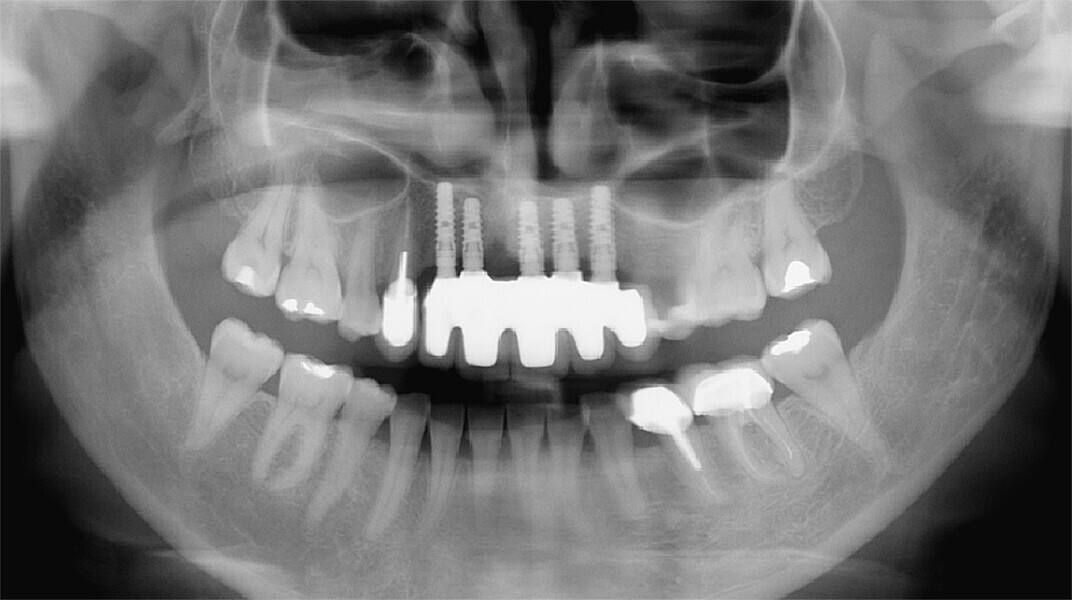

Fig. 10: Panoramic radiograph showing the grafts to be correctly healed and satisfactorily adhered to the recipient bone sites.

Fig. 40: Radiographic check-up after seven years.